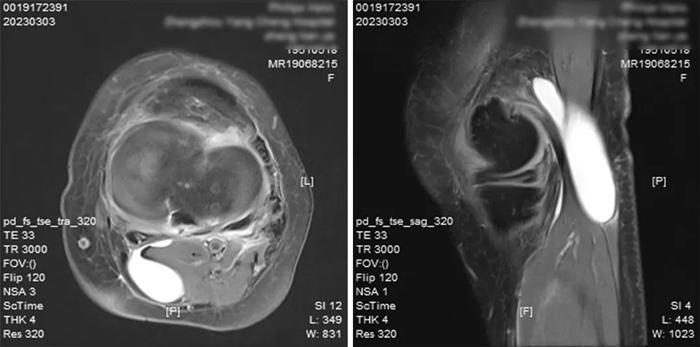

入院后根據(jù)鄭阿姨的病情及相關(guān)檢查

術(shù)前MRI檢查結(jié)果

確診為

左膝關(guān)節(jié)半月板損傷

左膝腘窩囊腫